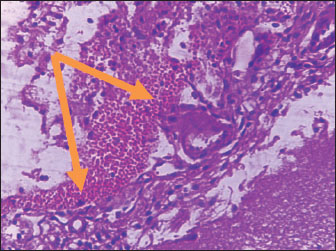

Brain of control group appeared normal structure of tissue with manifestation of Purkenji cells (Fig. 1), whereas sodium benzoate administration at low dose (200 mg/kg) occurred several histological lesions as hypertrophy of neurons (Fig. 2), pair nuclei arranged encompassed with clear space (Fig. 3), bleeding with degeneration of nerve cells (Figs. 4 and 5), respectively. In addition, lesions such as vacuolation, congestion, and accumulation of inflammatory cells were also evident (Figs. 6 and 7). However, severe histopathological lesions were observed following high-dose of sodium benzoate exposure, such as degeneration of neurons stained in dark blue (Fig. 8), prominent vascular duct with inflammation (Fig. 9), vacuolation, edema, and clear congestion as seen in Figures 1012, respectively.

Fig. 4. Points to the brain of sodium benzoate group (200 mg/kg): heavy hemorrhage (H&E) (100×).

Fig. 5. Points to the brain of sodium benzoate group (200 mg/kg): degeneration of neurons which stained in dark blue (H&E) (100×).